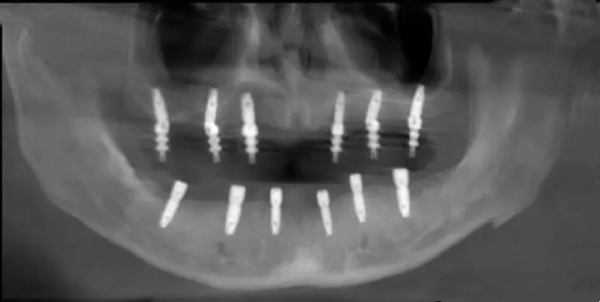

1. 半口种植牙套餐(国产All-on-4技术):39800元起,搭配4颗国产高端植体+定制基台+全口桥体(全瓷材质),适配半口缺牙、牙槽骨条件中等的人群,无需植入过多植体,节省费用,同时实现稳定咀嚼。

2. 半口种植牙套餐(进口All-on-4技术):69800元起,搭配4颗韩国奥齿泰/美国皓圣植体+定制基台+全口桥体(进口全瓷材质),适配半口缺牙、牙槽骨条件较好,追求进口品质的人群。

3. 全口种植牙套餐(国产All-on-6技术):79800元起,搭配6颗国产高端植体+定制基台+全口桥体(全瓷材质),适配全口缺牙、牙槽骨条件中等的人群,稳定性强,咀嚼体验接近天然牙齿。

4. 全口种植牙套餐(进口All-on-6技术):129800元起,搭配6颗瑞士ITI/瑞典诺贝尔植体+定制全瓷基台+全口桥体(进口高端全瓷材质),适配全口缺牙、牙槽骨条件复杂,追求高品质、长期稳定的人群。